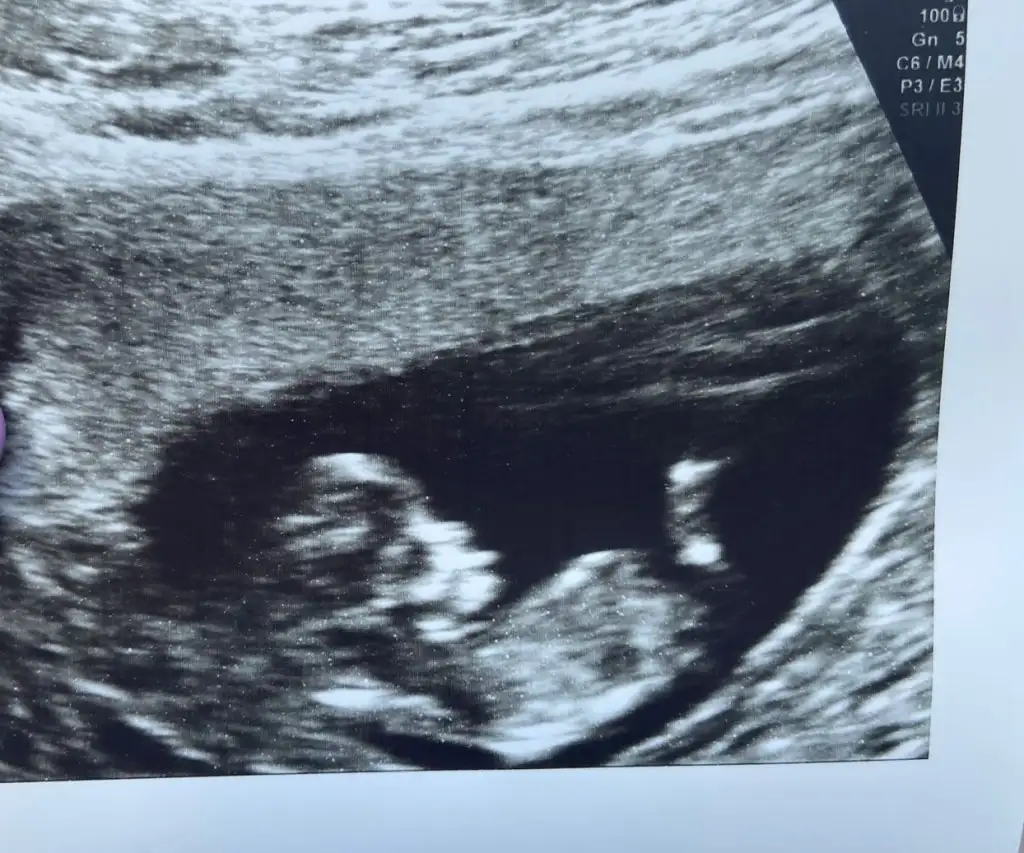

Erkek bebek gibi canım 2. Resimde. İlk foto vajinamı karından mı daha detaylı tek atarmısınikiside karından bakıldı. ilk ultrason 8. hafta ikincisi se 12. haftaya ait. Çok teşekkür ederim şimdiden

Eki Görüntüle 3270094 Eki Görüntüle 3270095